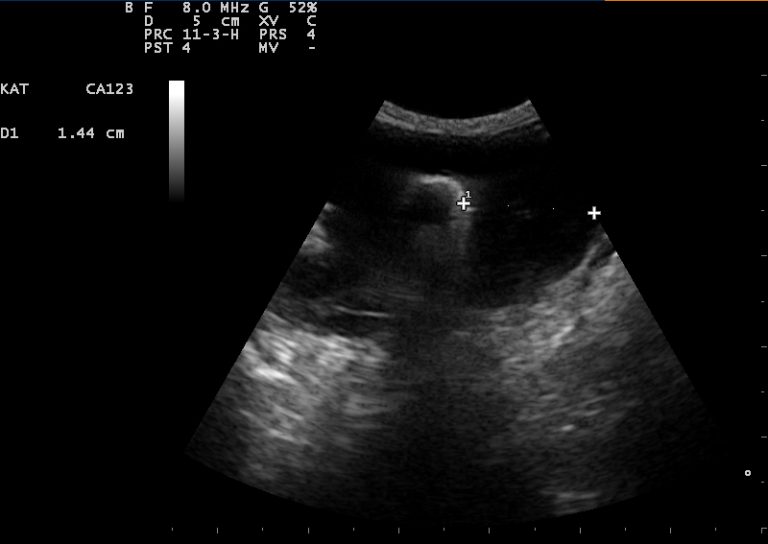

Echografie

Behalve voor drachtecho’s, waarbij we kijken naar het aantal pups bij een drachtige hond, kat, konijn, cavia of fret, wordt het echografisch onderzoek nog voor veel andere onderzoeken gebruikt.

Om beter inzicht te krijgen wat er zich ín het dierenlichaam afspeelt, is het mogelijk om een echo te maken. Hiermee kunnen we verschillende organen goed in beeld krijgen.

Tijdens de echo ligt uw huisdier op de rug op een kussen (voor een buikecho) of op de zijde op een speciale tafel (voor een hartecho). De buik of het gebied van het hart worden geschoren, waarna er speciale echo-gel op de buik of borst wordt aangebracht. Dit zorgt voor een direct contact van de echo-probe met de huid, zonder dat er hinderlijk lucht tussen zit, die het beeld kan verstoren.